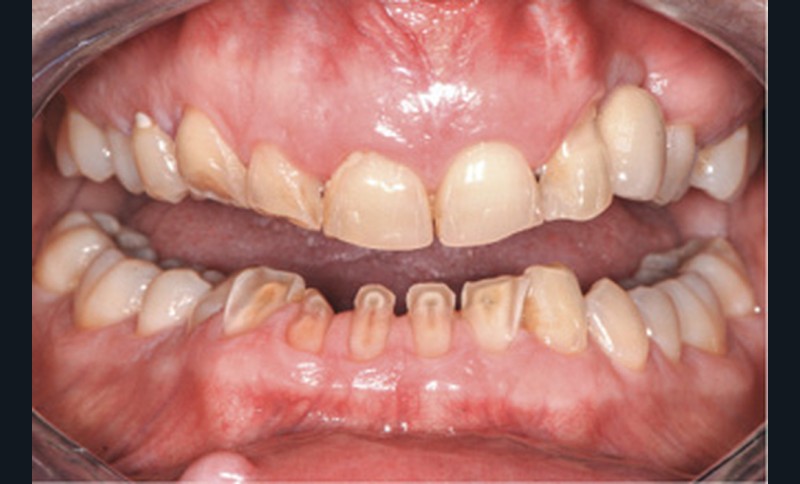

Lors de l’observation des arcades dentaires, il est constaté :

- une position mandibulaire en Occlusion d’Intercuspidie Maximale (OIM) reproductible, calée, non décentrée transversalement, c’est-à-dire physiologique ;

- l’usure particulière des dents du bloc incisivo-canin mandibulaire (fig. 2) ;

- les dents postérieures sont saines, naturelles et sans malposition ;

- une Dimension Verticale d’Occlusion (DVO) naturelle vraisemblablement conservée.

Certaines dents antérieures mandibulaires sont réduites pratiquement jusqu’à la…